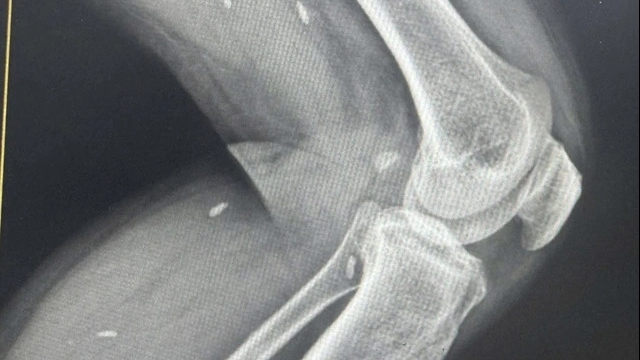

![]() |

| Ekip phẫu thuật tiến hành lấy thận của người hiến |